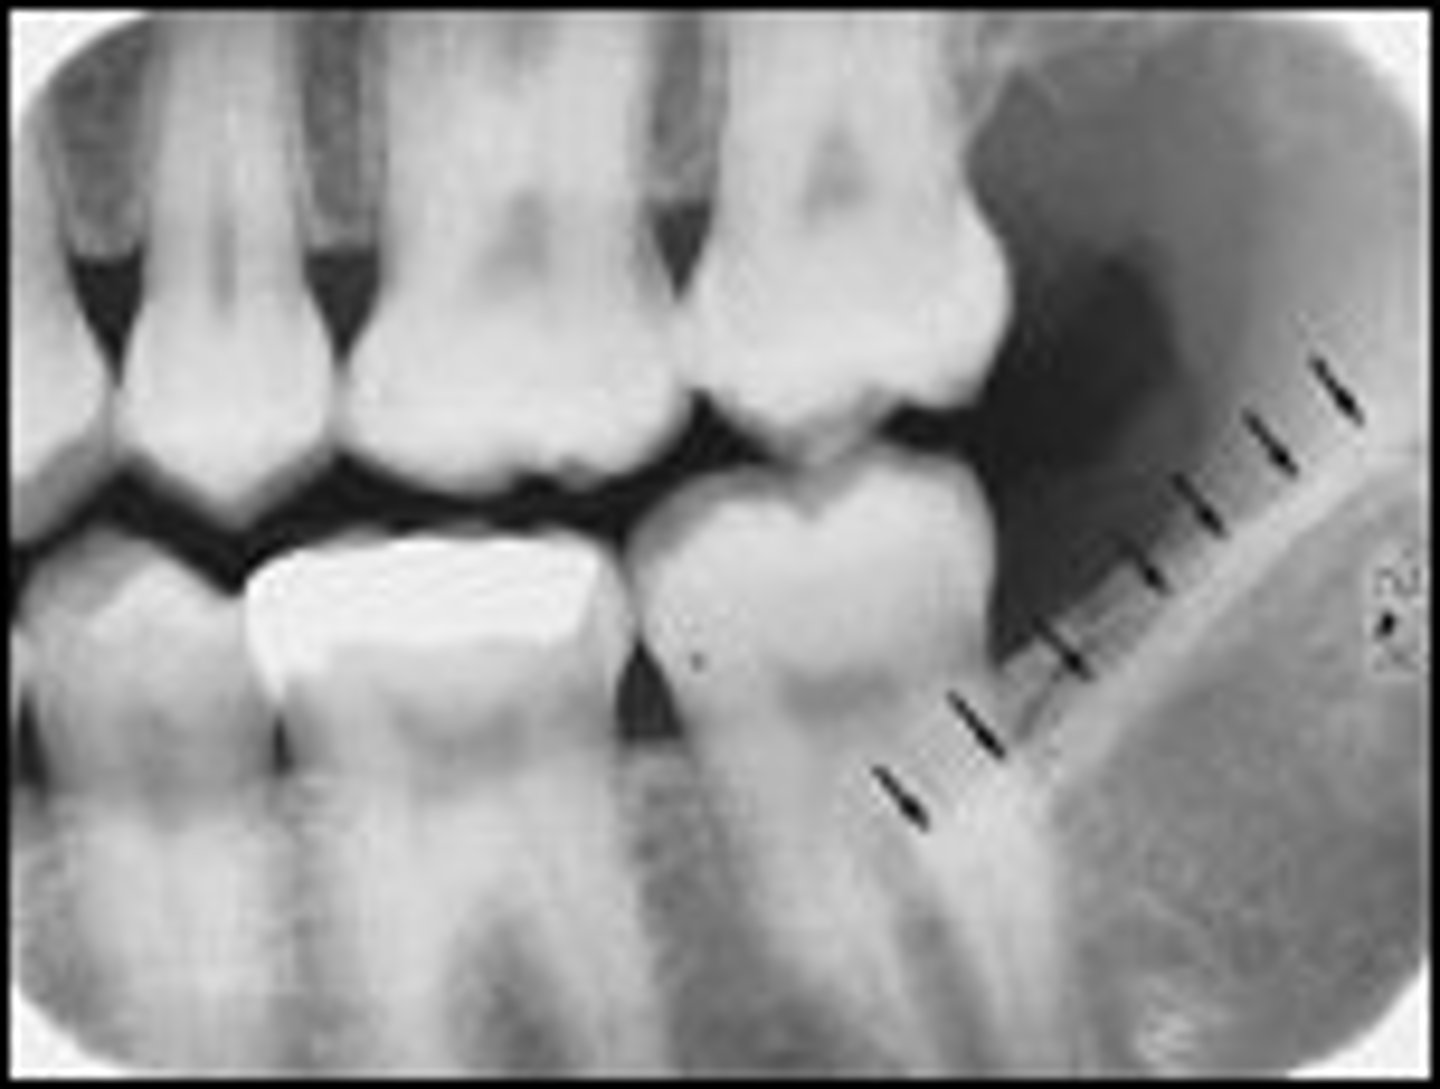

External oblique ridge

What is the radiopaque structure seen here?